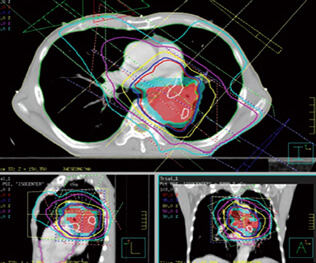

4차원 방사선 치료(4D RT)는 기존의 방사선 치료 기술을 한 단계 더 발전시킨 혁신적인 치료 방법입니다. 4D RT는 시간에 따른 조직 및 종양의 움직임을 고려하여 방사선 치료를 계획하고 제공하는 방법입니다. 3차원 방사선치료와 달리, 4D RT는 환자의 호흡, 심장 박동 등 생체의 움직임을 고려하여 치료를 계획하고 제공함으로써 정확도와 효과성을 높입니다. 이는 특히 호흡에 따라 위치가 변하는 폐암, 간암 같은 질병의 방사선 치료에 획기적인 정밀도와 효율성을 제공합니다.

4차원 방사선치료(4D RT)는 방사선 치료 과정 중 발생하는 환자의 움직임을 고려하여, 실시간으로 종양의 위치와 모양 변화를 추적, 분석하여 방사선을 조사하는 기술입니다. 이는 호흡기계, 심혈관계 등의 움직임 및 변화에 대응하기 위해 개발되었습니다.

4D RT는 환자의 호흡이나 움직임으로 인해 발생하는 시간적 변화를 고려하여, 치료해야 할 종양 위치에 정확히 방사선을 조사하는 것을 목표로 합니다. 이를 위해, 환자의 움직임을 추적하는 여러 기술이 사용됩니다. 이러한 기술의 도입으로 인해 다음과 같은 목적을 달성할 수 있습니다.

첫째, 종양의 정확한 위치를 실시간으로 파악함으로써, 방사선의 정확한 조사가 가능합니다. 이는 방사선 치료의 정확도를 크게 높여줍니다.

둘째, 정확한 조사를 통해 주변 정상 조직에 미치는 피해를 최소화합니다. 이는 환자의 회복 시간 단축 및 치료 부작용의 감소를 의미합니다.

셋째, 종양 조직에보다 집중적으로 방사선을 조사할 수 있게 되어, 치료 효과를 극대화할 수 있습니다.